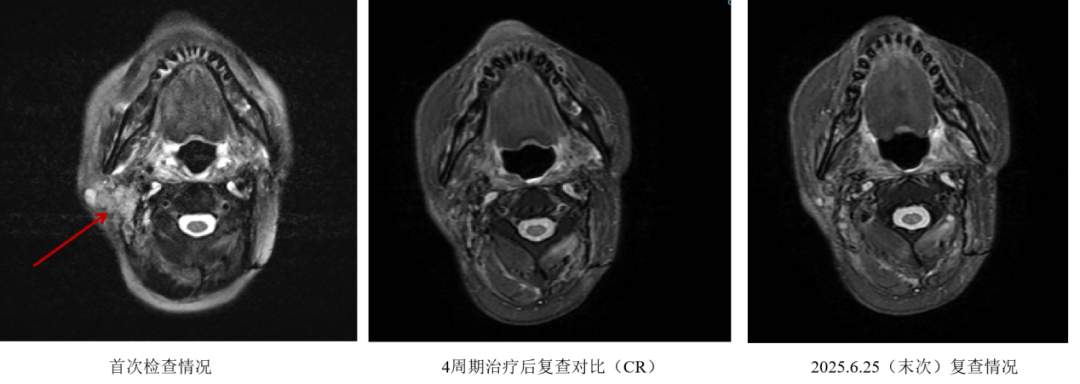

• 患者于2023年09月13日返院复查影像,肿瘤评估疗效CR。

• 2023年10月,患者已完成4周期艾托组合抗体+GP治疗,根据研究方案,后续周期可予艾托组合抗体单药维持。2023年10月24日—2024年09月18日,患者行第5-19程艾托组合抗体注射液260mg单药维持。

疗效评估

4周期艾托组合抗体+GP治疗后,评估疗效CR,且后续持续保持CR(截至2025年6月18日末次门诊复查)。

11.png

图2 影像学评估疗效

本病例展示了一位病程长达十年的鼻咽癌患者复杂而颇具启示性的治疗历程。患者于2015年接受初始治疗(同步放化疗),后在2020年经历首次复发(接受手术联合放化疗),至2022年再次出现复发(表现为右侧腮腺淋巴结转移)。对于此类既往已接受手术及多轮放化疗后仍出现多次复发的患者,后续治疗选择通常极为有限,且整体预后普遍不佳,临床管理面临严峻挑战。然而,本例患者在接受4周期艾托组合抗体联合化疗治疗后,疗效评估达到了令人鼓舞的CR。更值得关注的是,在后续长达15周期的艾托组合抗体单药维持治疗下,患者的CR状态得到了持续巩固。截至末次随访,其无瘤生存期已突破21个月,标志着患者实现了长期疾病控制。